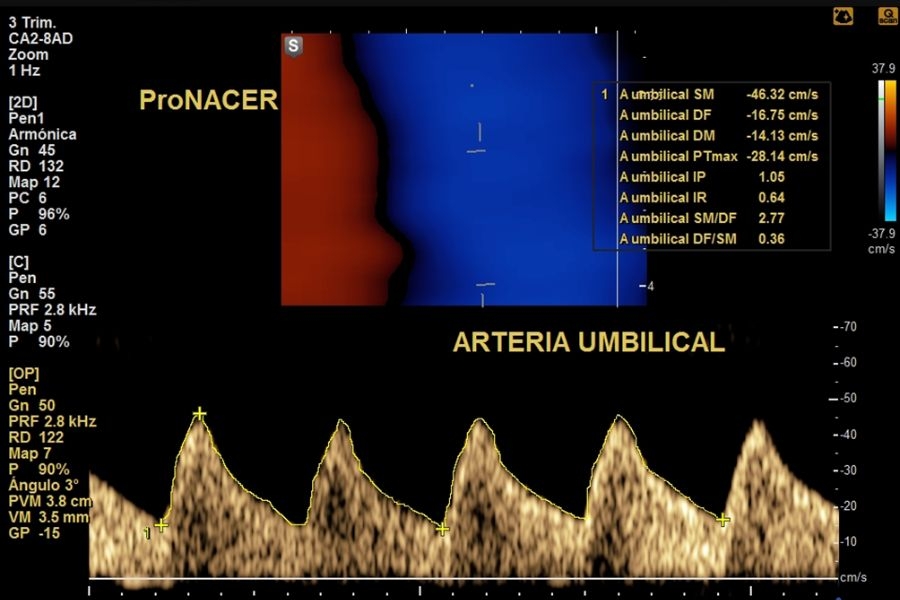

Se controlan más estrechamente a las gestaciones MONOCORIALES (con una sola placenta). Las gestaciones con gemelos monocoriales son embarazos de mayor riesgo debido al mayor riesgo de complicaciones que pueden tener con respecto a las gestaciones bicoriales (dos placentas).